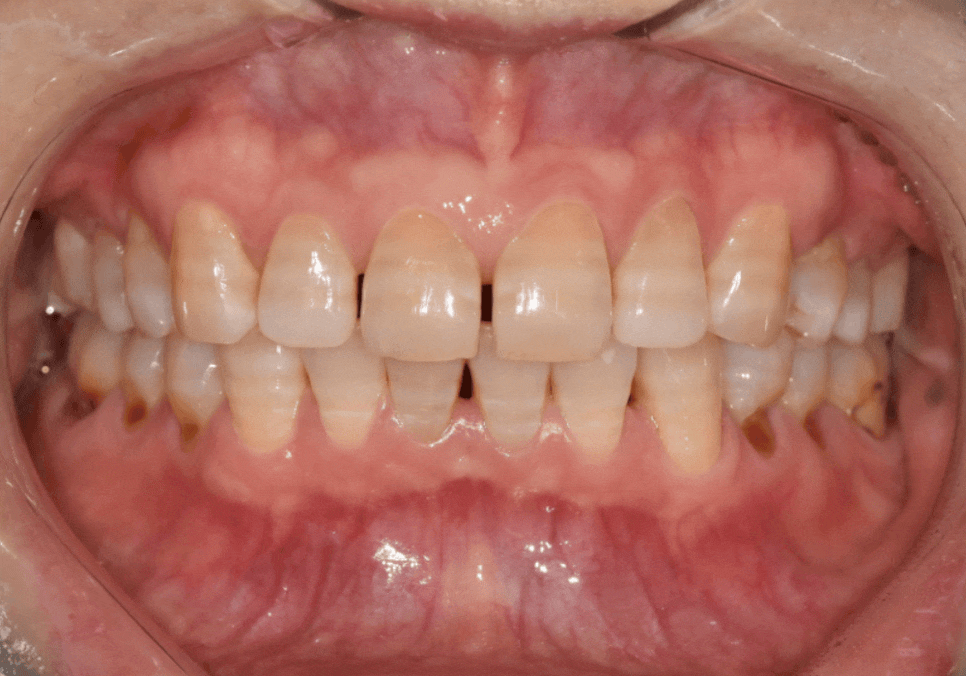

라미네이트로 개선한 실제 사례

얼마 전에 내원하신 한 환자분이 특히 기억에 남습니다.

앞니가 벌어져 있고,

갈색 가로줄이 선명하게 보여서 웃을 때마다

입을 가리게 된다고 하셨습니다.

250220

자세히 보니 전형적인 항생제 변색이었습니다.

앞에서 말씀드린 것처럼 항생제 변색은

치아 내부 깊숙이 색소가 침착되어 있어서

치아미백효과를 거의 기대하기 어렵습니다.

대신, 라미네이트로 치아 벌어짐과 변색을

동시에 해결하는 것이 가장 효과적이라고 설명드렸습니다.

환자분도 오랜 고민 끝에 결정하셨고,

웃을 때 가장 잘보이는

앞니 4개를 라미네이트로 진행했습니다.

치아 벌어짐을 자연스럽게 메우면서도

치아가 너무 커 보이지 않도록

크기와 비율을 꼼꼼하게 맞춰 드렸습니다.

색상은 환자분이 원하시는 밝기 범위 안에서,

자연스럽고 건강해 보이도록 제작했습니다.

완성 후에는 갈색 가로줄도 보이지 않게 되었고,

치아 색도 밝고 균일하게 정돈됐습니다.

치아 벌어짐도 자연스럽게 메워져서

웃을 때 자신감이 생겼다고 하셨습니다.